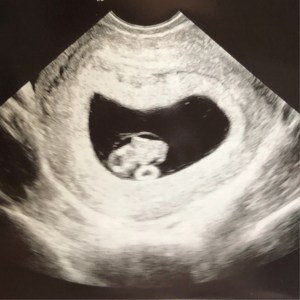

By the time we had our first appointment at 8 Weeks, the nausea had actually gotten significantly better. And we got to see Baby B’s heart beat for the first time!! 😍😭 It was so surreal. We had already taken 3 pregnancy tests at home, I was exhibiting symptoms (like my boobs actually growin’ like 1/2 a cup size!), and the OB had confirmed our pregnancy with my urine test & palpation of my abdomen. BUT of course, we both were still like “ok….. but we still need to SEE it” 😂 And BAM! There it was. Our tiny little nugget, with its heart beatin’ like crazy… right inside of MY body. It was beautiful ❤️